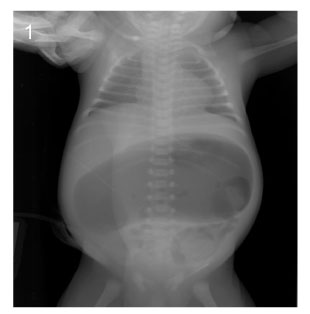

Fig. 3

Image of simple X-ray at the age of 43days (Case No. 4).

Fig. 3 Image of simple X-ray at the age of 43days (Case No. 4).